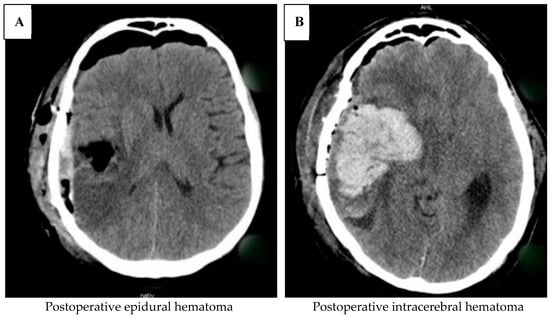

Intracranial Hemorrhage

- Hemorrhage in the tumor cavity;

- Intracerebral hemorrhage;

- Subarachnoid hemorrhage;

- Subdural hemorrhage.